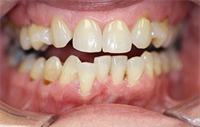

Dentaltown Learning Online- The Aesthetic Full Mouth Rehabilitation by Dr. John Nosti

Dentaltown Learning Online is proud to present John Nosti's latest extraordinary CE course...."The Aesthetic Full Mouth Rehabilitation" This course can be found here... Full Mouth Rehabilitations are one of the most difficult types of cases to handle in practice today. Many times these patients...  Read More